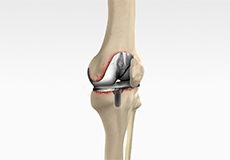

ACL Tears

The anterior cruciate ligament (ACL) is one of the major ligaments of the knee. It is located in the middle of the knee and runs from the femur (thighbone) to the tibia (shinbone). The ACL prevents the tibia from sliding out in front of the femur. Together with the posterior cruciate ligament (PCL), it provides rotational stability to the knee.